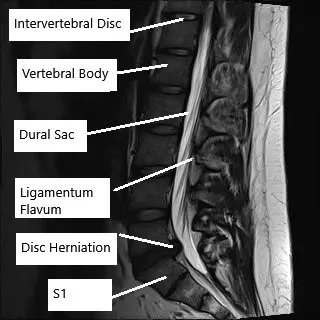

With microdiscectomy, the spine surgeon aims to relieve the pressure off the spinal nerve roots. The spinal nerve roots in the lower lumbar spine run inside a protective covering dural sac. The dural sac runs inside the central canal formed by the consecutive vertebrae.

At each spinal level, the spinal nerves exit through a narrow opening called the intervertebral foramen. The lumbar and sacral spinal nerves continue to supply different regions of the lower extremities and also control the bladder and bowel movements.

Intervertebral discs are present in between the consecutive vertebrae and a herniation of the intervertebral disc may put pressure on the spinal nerves or the dural sac. The spinal nerves may also be compressed by bone spurs or an enlarged adjacent facet joint. The compression of the spinal nerves leads to irritation and symptoms of back pain that may radiate down the legs. The patients may also experience symptoms such as numbness or tingling sensation in the lower extremities.